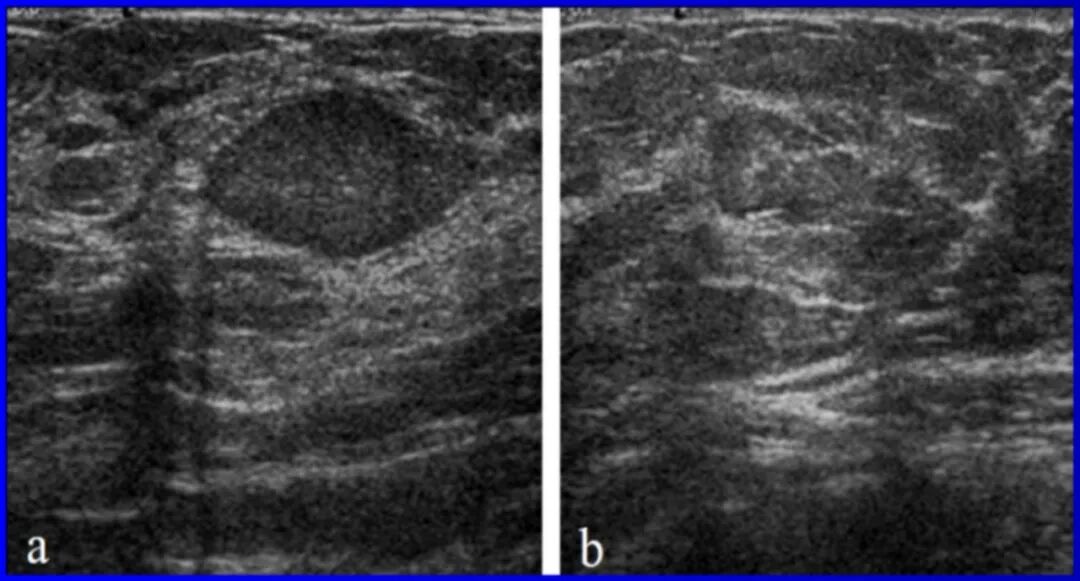

乳腺彩超和乳腺钼靶是最常规的两种乳腺检查,是两种完全不同的检查手段。经常发现有很多人对于乳腺彩超和乳腺钼靶两种检查手段的区别存在疑惑,甚至存在误解,有时只愿意选择其中的一项检查,其实两种检查方式截然不同,不可相互替代,在临床上可以相互补充。

适合任何年龄段的女性筛查,即便是在孕期和哺乳期,它也是最为安全的检查方式,不需要担心辐射问题。

乳腺的彩超和乳腺的钼靶,是目前临床中最常见、最简便的两种检查方法。这两种方法不存在哪一种比另一种更好的说法,它们在临床中作用是互补的,比如对于年轻患者的乳房结节,以及诊断重点在腋窝或锁骨上、下的淋巴结,彩超比钼靶的效果更好,但对于年龄较大,尤其是绝经后的患者,通常钼靶要好于超声。另外,钼靶可以发现一些超声不能发现的钙化,而对于有乳头溢液的患者,钼靶可以通过造影发现乳管内的病变。